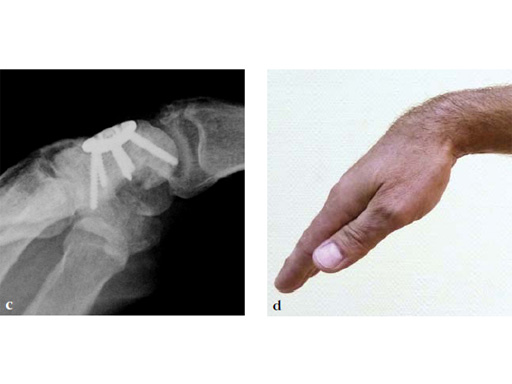

Fig 5cd Plate positioning and fixation. The combined VA-locking-standard guide allows drilling in the appropriate direction.

Fig 6ab Final appearance of fixed plate.

Fig 7ab No impingement of the plate against the dorsal rim of the radius in extension.